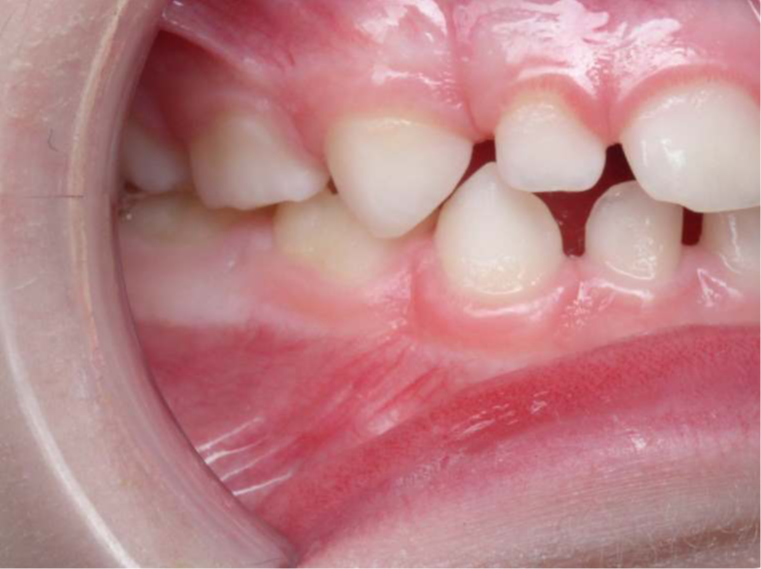

bilan début et fin de traitement